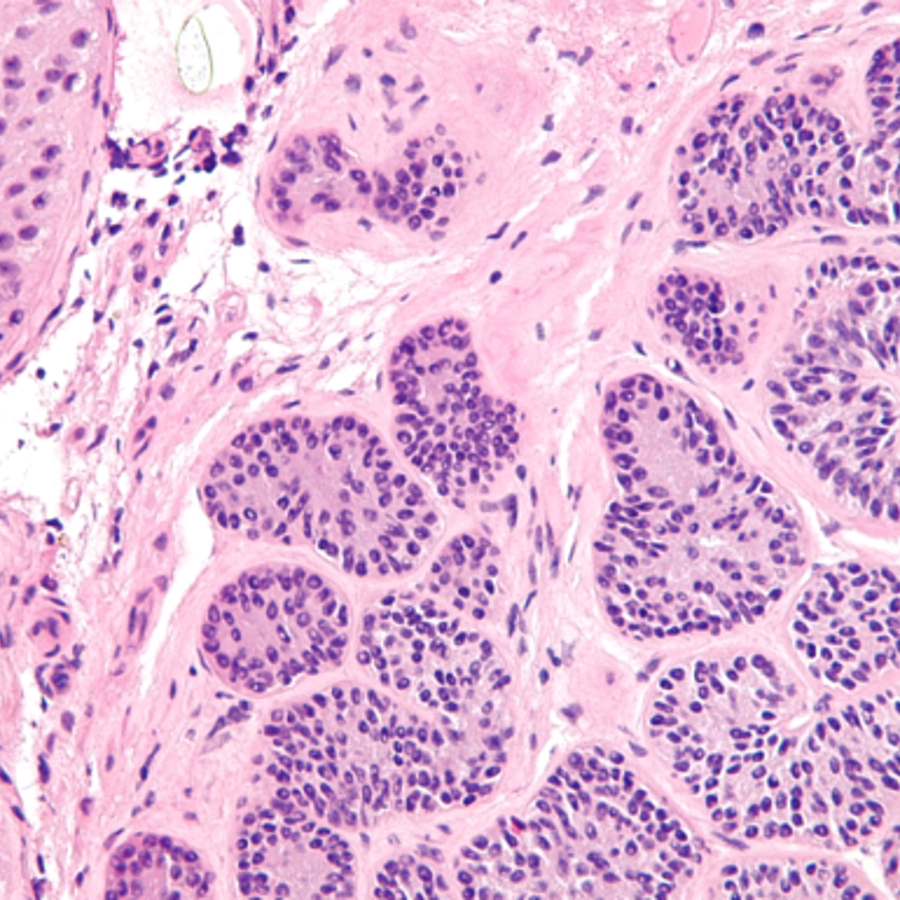

This is what Sertoli cells look like under the microscope at high resolution. Via Wikimedia Commons